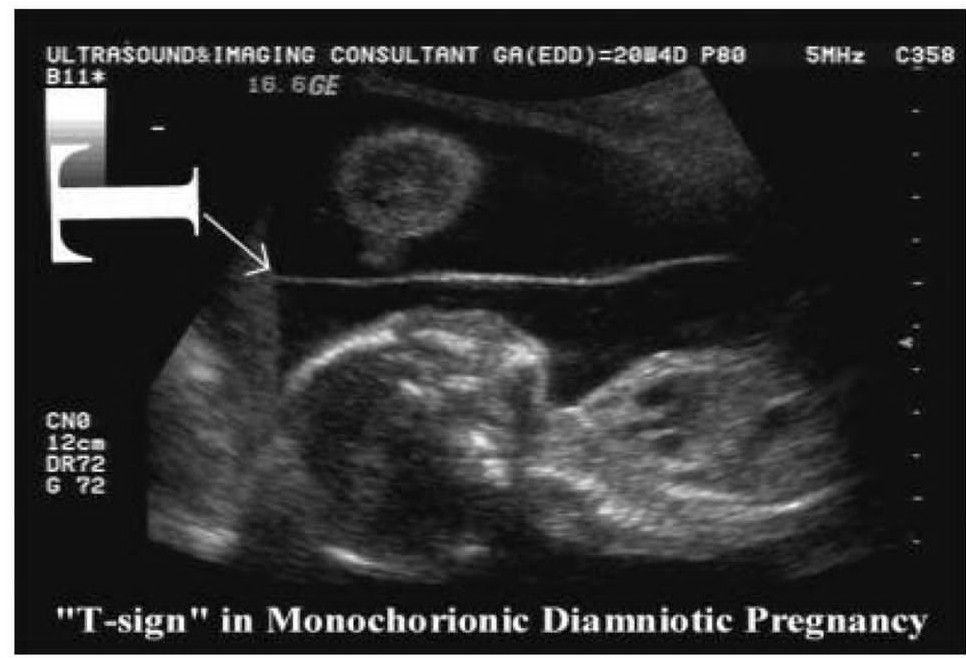

The "T sign" is really the absence of a twin-peak sign (or lambda (λ) sign) and is used in ultrasound assessment of a multifetal pregnancy. It refers to the lack of chorion extending between the layers of the intertwin membrane, denoting a monochorionic pregnancy.